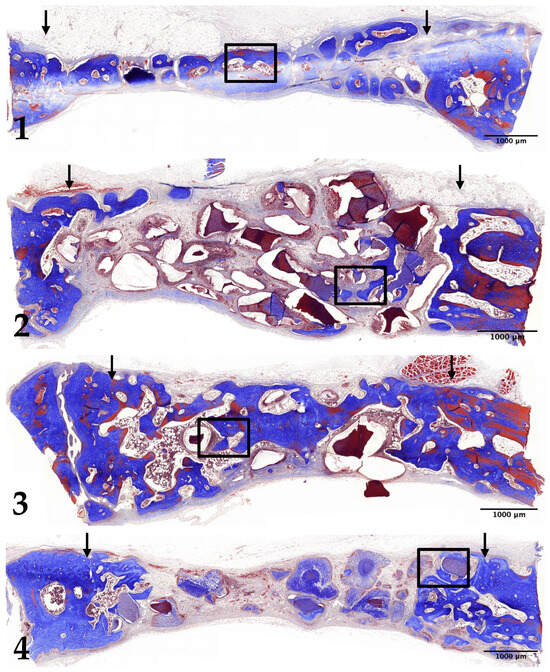

3.4. Eight-Week Results

3.5. Histomorphometric Analysis: New Bone Formation

3.6. Histomorphometric Analysis: Decrease in Remaining Graft Material Area

3.7. Histomorphometric Analysis: Quantifying Changes in Bone Marrow Area